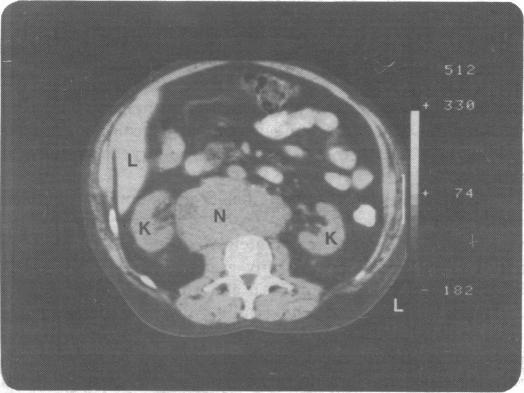

Computed tomography of the body: when should it be used?

Br Med J (Clin Res Ed). 1982 Jan 2;284(6308):4-8. doi: 10.1136/bmj.284.6308.4.